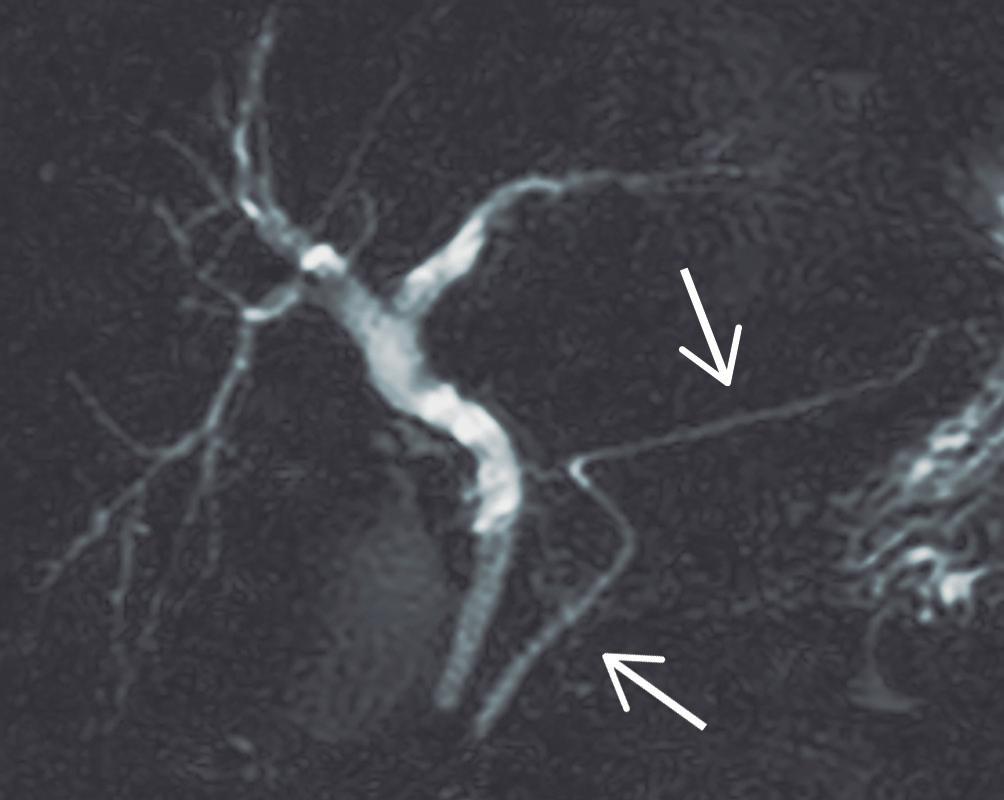

Manifestaciones ductales

Los cambios ductales de la PAI, si bien han sido descripto para CPRE, pueden ser documentados de manera muy elocuente por colangio-RM. Se utilizan secuencias radiales, con diferentes ángulos de rotación, orientando la adquisición específicamente al conducto pancreático, así como también secuencias volumétricas que permiten reconstruir la vía biliar y el conducto pancreático en 3 dimensiones. Los criterios ductales aceptados son la estenosis prolongada (> 1/3 de la longitud) del conducto pancreático o bien estrechamientos multifocales en diferentes sectores de la glándula. Suele observarse una leve dilatación ductal, proximal a la estenosis. La visualización del conducto pancreático dentro de la lesión parenquimatosa es conocida con el nombre de “signo del conducto penetrante” y es característico de los procesos inflamatorios, a diferencia del cáncer, donde la señal del conducto se interrumpe de manera abrupta.

Figura 9. Manifestaciones ductales

9a 9b

9a. Colangio-RM: Estenosis larga, mayor a 1/3 de la longitud del conducto pancreático, pudiendo observar la señal ductal atravesando el sitio de la obstrucción, hallazgo conocido como “signo del conducto penetrante” (flecha blanca). A diferencia del ACDP, en la PAI, la dilatación proximal a la obstrucción es leve (flecha amarilla).

9b. Colangio-RM: Múltiples estenosis de corta extensión en diferentes sectores del páncreas.